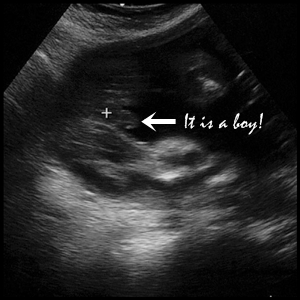

不過,檢驗師送我們走之前還要我們別擔心,說是男寶寶這種現象還滿正常的。

說到男寶寶,我們終於確認性別了,很高興是老公喜歡的男孩,